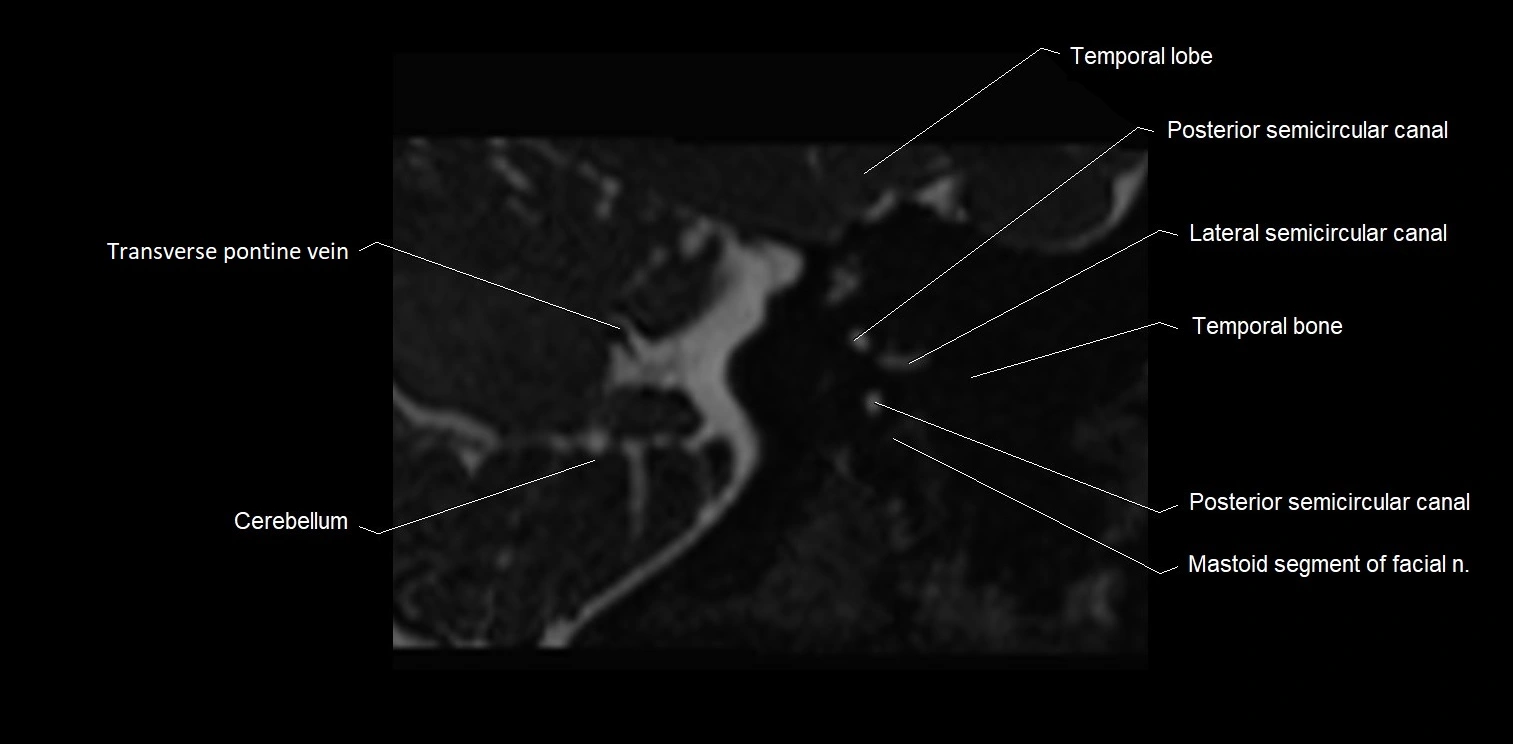

MRI images

image